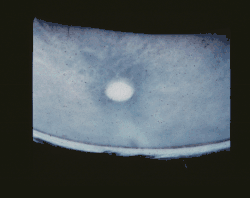

Choroba ujawnia się w wieku młodzieńczym. Pierwszymi objawami, pojawiającymi się między 4. a 10. rokiem życia, są zanik nerwu wzrokowego i zwyrodnienie barwnikowe siatkówki, prowadzące do ślepoty[3]. Między 6. a 18. rokiem życia pojawiają się napady padaczkowe. W drugiej dekadzie życia dołączają się zespół parkinsonowski i mioklonie.